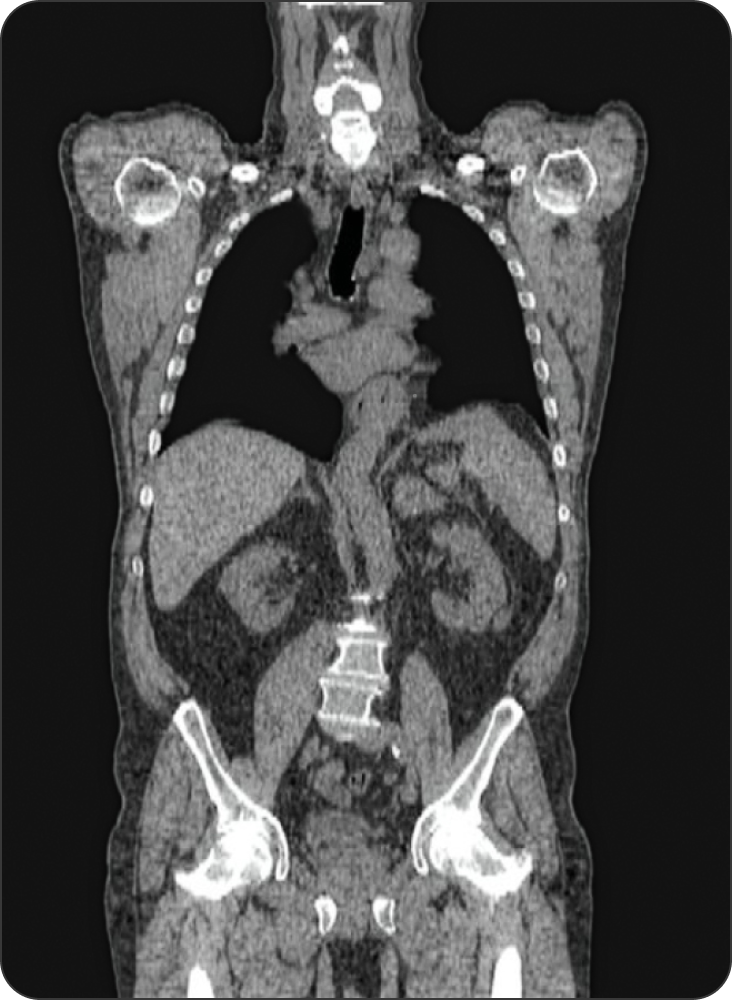

Ctscanxlg

Tratar lo que ves

Los isótopos radiactivos se pueden utilizar en el diagnóstico por imagen y en aplicaciones terapéuticas, lo que permite un enfoque de “si puedes verlo, puedes tratarlo” para el tratamiento del cáncer.1a